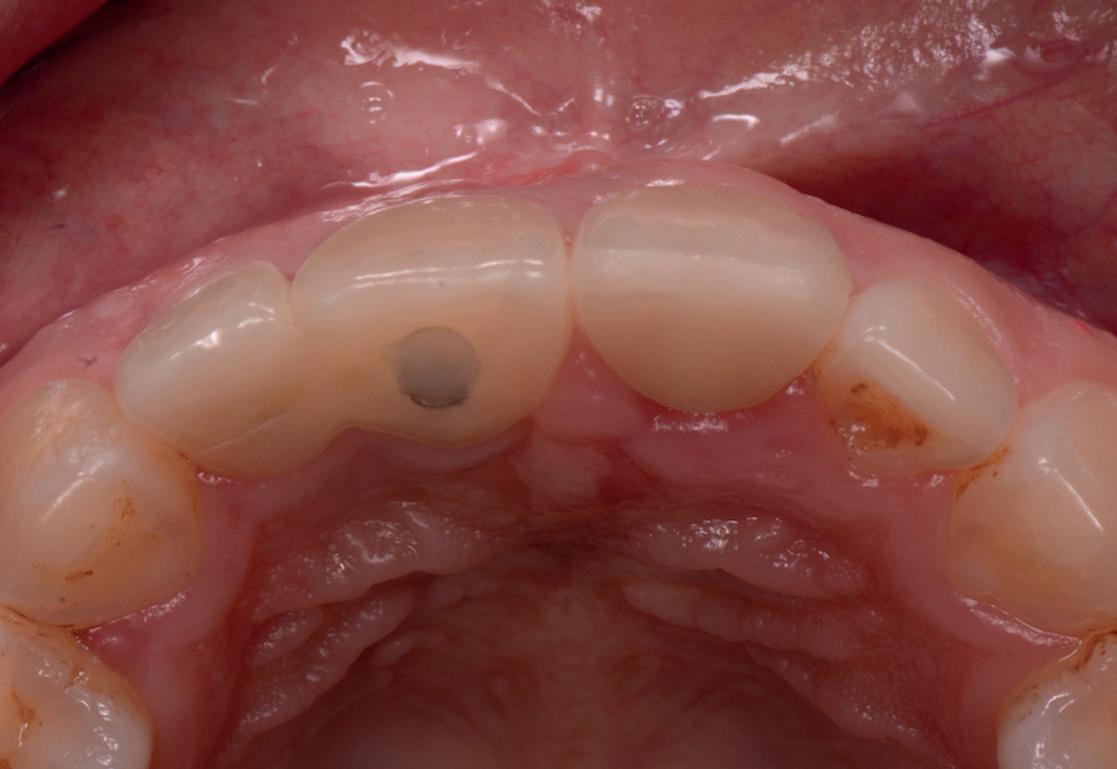

RECONSTITUIREA țesuturilor moi periimplantare. Scopul acestui raport de caz este de a demonstra procedurile chirurgicale utilizate pentru corectarea unui defect al țesuturilor moi periimplantare folosind țesutul moale interdentar în combinație cu tuberozitatea ca locație donatoare de țesut conjunctiv, utilizând o abordare prin tunelizare într-o zonă estetică.

Totuși, ca și în cazul implanturilor de titan, în rare cazuri, și la cele ceramice poate apărea o recesie nedorită cu expunerea umărului implantar. Cu toate acestea, din punct de vedere estetic, această recesie a gingiei inflamate este posibil să fie mult mai bine tolerată de către pacienții preocupați de marginile întunecate ale implanturilor de titan (fig. 2).

Trebuie remarcat, totuși, că în cazul implanturilor ceramice, ca și în al celor de titan, cementita, adică inflamația periimplantară cauzată de reziduurile de ciment, poate duce la periimplantită. În plus, la implanturile din dioxid de zirconiu poate apărea supraîncălzirea la înșurubarea implantului în os, iar suprafețele excesiv de aspre sau poroase ale implantului pot cauza defecte osoase periimplantare din cauza termoconductivității reduse a materialului. Deși sunt necesare mai multe dovezi științifice care să demonstreze o tendință mai scăzută spre periimplantită în cazul implanturilor ceramice, argumentul esențial pentru aceste implanturi bazat pe experiența clinică este starea excelentă și aproape constant lipsită de inflamație a țesuturilor moi periimplantare (fig. 3).

1. Implanturi din titan (stânga) și zirconiu (dreapta). 2. Recesii la implanturile ceramice (stânga) și din titan (dreapta). 3. Țesut moale cu implant din zirconia, lipsit de inflamație.